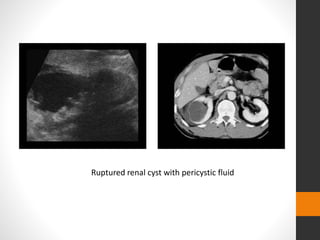

Ruptured renal cyst with pericystic fluid